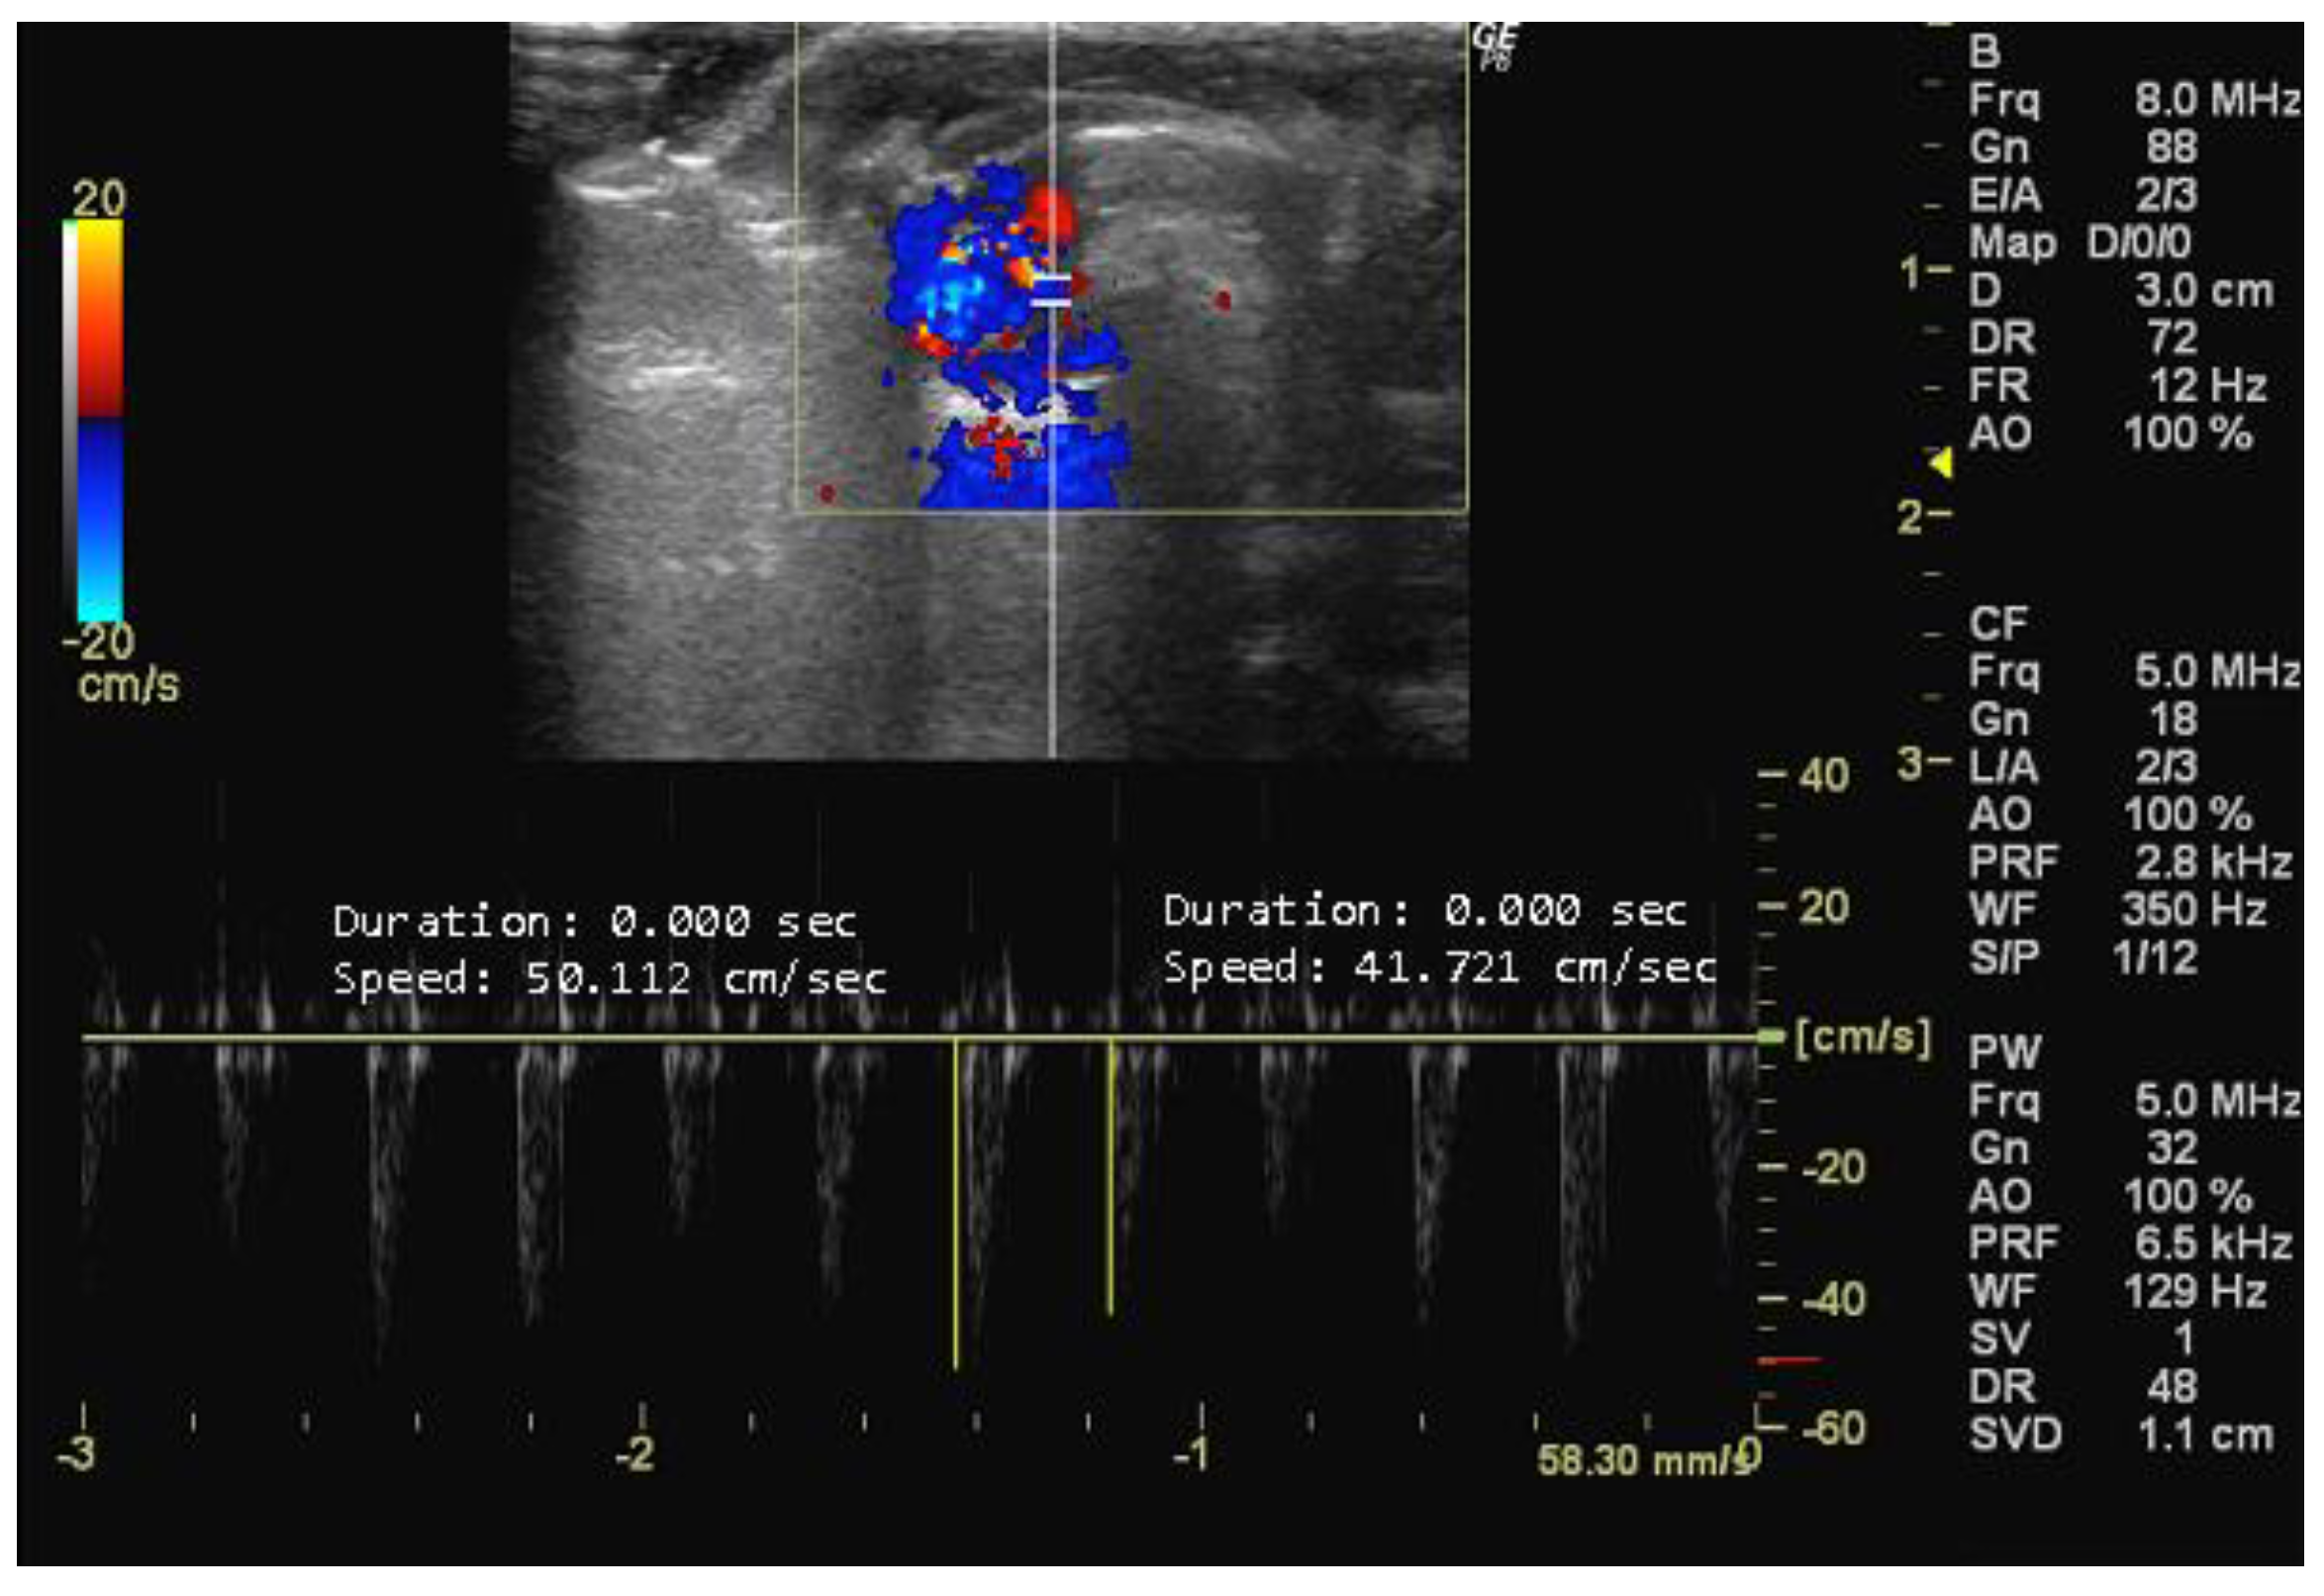

- How to measure E and A peaks